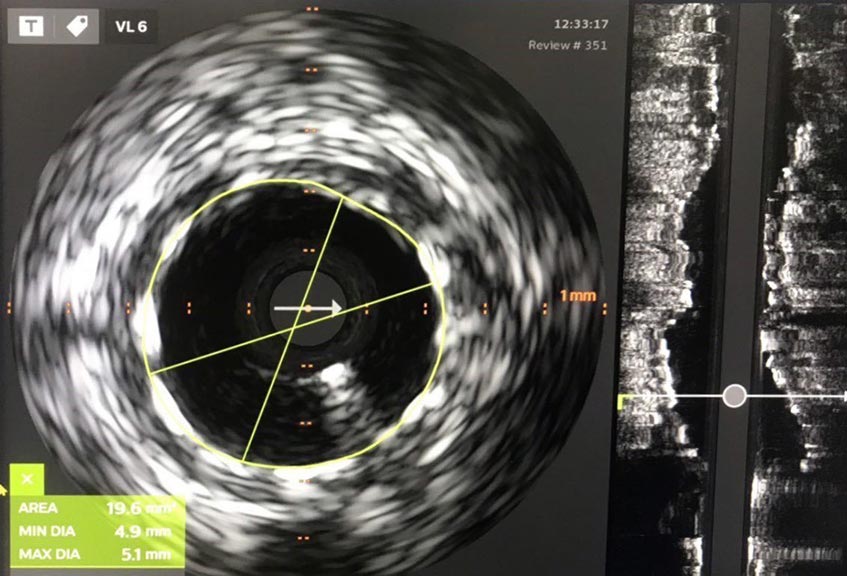

Hiện nay, Trung tâm Can thiệp mạch Bệnh viện Đa khoa Tâm Anh TP.HCM đã cập nhật những thế hệ stent hiện đại của thế giới. Đó là các loại stent tự tiêu, stent có phủ thuốc chống viêm, chống tái hẹp hiệu quả cao; có độ đàn hồi thấp giúp stent không bị gãy hoặc co lại do đàn hồi của mạch máu. Bên cạnh đó, với sự hỗ trợ của kỹ thuật siêu âm trong lòng mạch (IVUS) giúp xác định đường kính tối đa của mạch máu, các bác sĩ chọn được loại stent phù hợp và có thể nong từ stent đường kính 3.5mm đến kích thước 5.0mm, không bị gãy. Lòng mạch càng mở rộng, tưới máu càng hiệu quả và ít tái hẹp về sau.